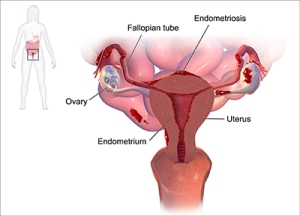

The complaint is often one of almost incapacitating pain in the pelvis and lower back which is at its worse during ovulation, menstruation or sexual intercourse. This is made possible by uterine tissue attaching itself to other organs, e.g. the fallopian tubes, ovaries, on the outside of the uterus, bladder, and even the lungs where it continues to function as if it were still in the womb. Hence they fill up with blood every month, but unlike menstrual blood which is released by the vagina, this blood remains in the tissue spaces and form cysts which can in turn grow large enough to bind organs together.

The complaint is often one of almost incapacitating pain in the pelvis and lower back which is at its worse during ovulation, menstruation or sexual intercourse. This is made possible by uterine tissue attaching itself to other organs, e.g. the fallopian tubes, ovaries, on the outside of the uterus, bladder, and even the lungs where it continues to function as if it were still in the womb. Hence they fill up with blood every month, but unlike menstrual blood which is released by the vagina, this blood remains in the tissue spaces and form cysts which can in turn grow large enough to bind organs together.

One of the theories how uterine tissue is able to find itself in other areas of the body is that endometrial cells travel to the pelvic cavity through the bloodstream or the lymphatic system. Another is that it is caused when the body is still an embryo because endometrial cells of some foetuses don’t differentiate themselves and make the trip to the appropriate sites, thus ending up in the wrong places. Environmental oestrogens, and endocrine disruptors, also receive some of the blame. They take the forms of plastics, detergents, pesticides, household cleaners, etc.

One of the theories how uterine tissue is able to find itself in other areas of the body is that endometrial cells travel to the pelvic cavity through the bloodstream or the lymphatic system. Another is that it is caused when the body is still an embryo because endometrial cells of some foetuses don’t differentiate themselves and make the trip to the appropriate sites, thus ending up in the wrong places. Environmental oestrogens, and endocrine disruptors, also receive some of the blame. They take the forms of plastics, detergents, pesticides, household cleaners, etc.